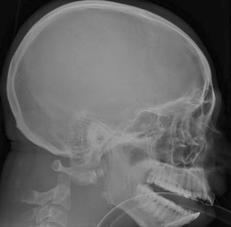

TRAUMA CERVICALA

Aspect normal Imagine

incompleta Aspect

normal

Incidenta occipitomentala (odontoida)

Aspect normal Incidenta

oblica

Aspect normal